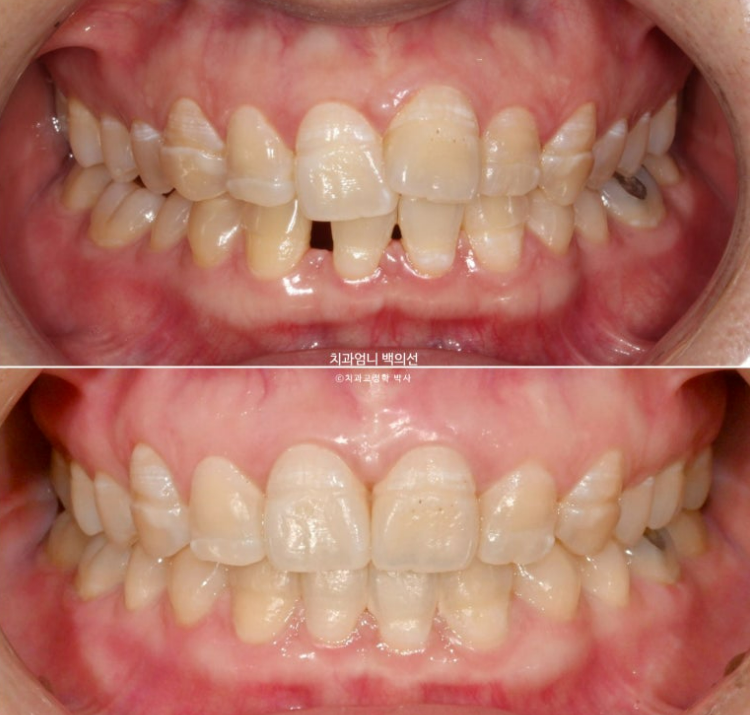

중심선은 정확히 맞고 앞니 교합도 좋습니다.

파란화살표는 사실 앞니가 아니라 송곳니 입니다.

어금니 교합관계는 정확히 1급입니다. 송곳니 자리에 있는 파란 화살표는 사실 송곳니가 아니라 첫번째 작은어금니입니다.

이제 전후 비교 보겠습니다. 총 치료기간은 1년 8개월입니다.

임플란트 없이 교정만으로 깔끔하게 마무리된 모습입니다.

양측 어금니 교합관계는 기존 3급에서 1급으로 개선되었고

앞니 덧니와 돌출이 해소가 되었습니다.